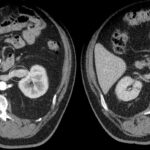

Fase nefrográfica o portal

Se logra a partir de los 80 a 180 segundos posteriores a la inyección del contraste; el medio de contraste se encuentra en los túbulos colectores y asa de Henle durante esta fase y su utilidad se basa en el aumento homogéneo del parénquima renal, lo que permite una mejor delimitación de la masa renal.

Durante esta fase se presenta el mayor realce de los tumores sólidos, por lo que se logra una mejor caracterización de las masas indeterminadas. En un estudio sobre la caracterización de las masas renales menores a 3 cm se concluyó que durante las exploraciones en fase nefrográfica se permitió una mayor detección de lesiones y una mejor caracterización de las masas renales pequeñas que en las exploraciones de fase corticomedular 3-5 (Fig. 3).